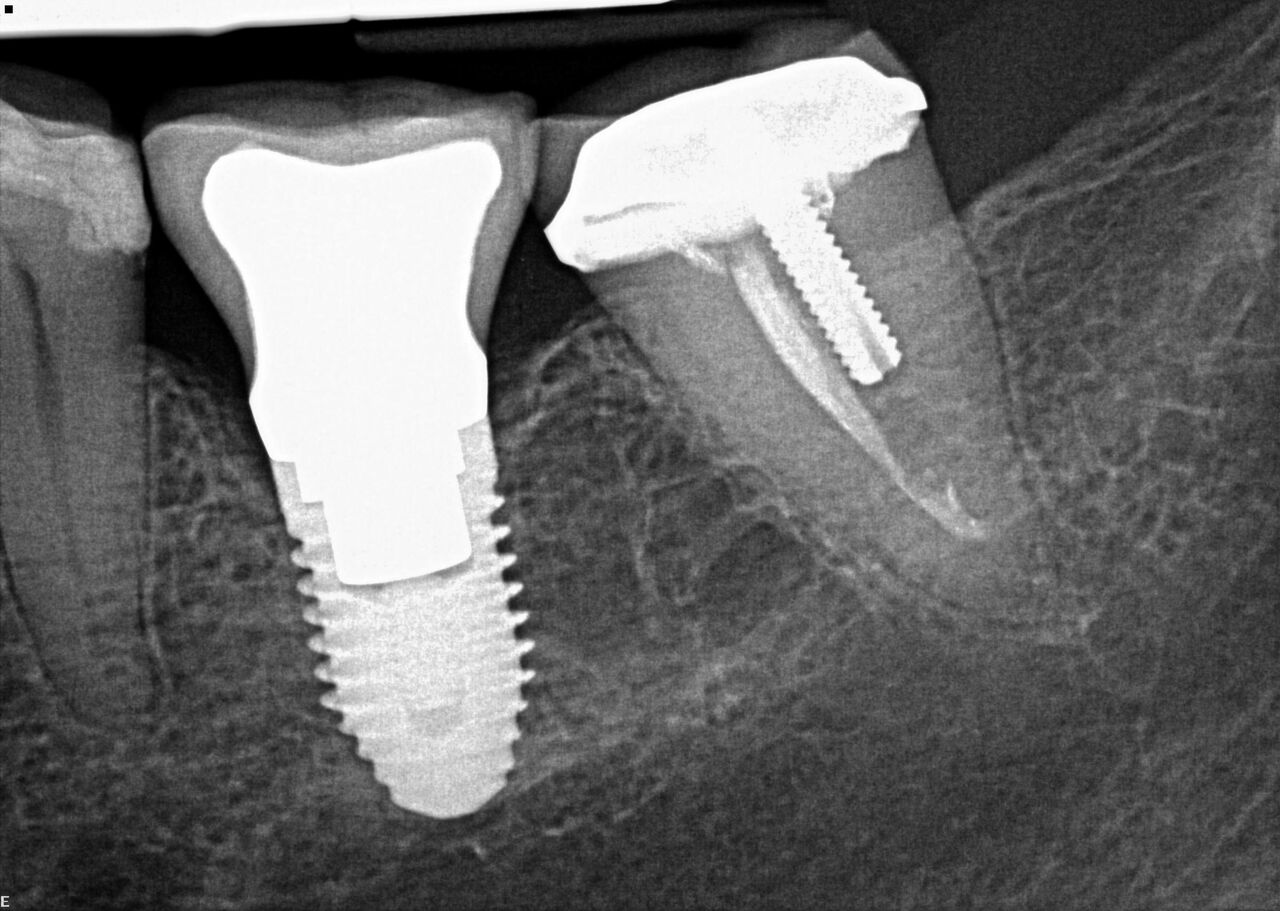

(14.) Integration confirmation on Nos. 12 and 13 at 6 months with temporary abutments and good soft tissue maturation.

Figure 14

(15.) Clinical view of final individual crowns on Nos. 12 and 13.

Figure 15

(16.) Radiograph of final restorations on Nos. 12 and 13. Notice platform shift in No. 12 restoration.

Figure 16

A 67-year-old woman presented on an emergency basis with a bad odor and taste from crown No. 12, which had been diagnosed that day at hygiene recall as decayed and no longer attached to the underlying root (Figure 8 and Figure 9). The patient was anesthetized and the existing bridge was sectioned (Figure 10), leaving crown No. 14 intact. The No. 12 root was extracted and the site was fully debrided of granuloma. A platform shift implant was stabilized in excess of 45 Ncm in position No. 12, which was prosthetically correct. The soft tissue of pontic site No. 13 was contoured to mimic soft tissue contours of a bicuspid and an implant was secured in excess of 45 Ncm. Implant No. 13 was milled to allow for unimpeded seating of the temporization abutment, whereas implant No. 12 did not need milling as it was a platform-shift implant. The existing crown No. 12 and cantilever No. 13 were revised to be a temporary bridge on Nos. 12 and 13 (Figure 11 and Figure 12). The revised temporary bridge was positioned in infraocclusion and cemented after the extrusion of excess cement extraorally (Figure 13). No bone graft or sutures were placed as the temporary crowns sealed the sockets.

The patient was prescribed antibiotics and analgesics and instructed in postoperative care particular to immediately provisionally restored implants. At 6 months, integration was confirmed (Figure 14) and the patient returned to her dentist for restoration. The implants were restored with individual cement-retained crowns with a platform shift for No. 12 restoration from the 6-mm diameter of the implant to a 5-mm diameter of the final restoration (Figure 15 and Figure 16).